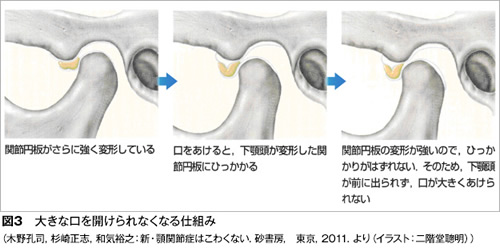

顎関節症の病気の状態(病態)は現在4つに分類されています。最も多いのは関節内にある関節円板(図1)というクッションが前方にずれることで起きる「カクンカクン」という音が出る状態(図2)、あるいはずれがもっと大きくなることで大きな口が開けられなくなる状態です(図3)。

特に口が大きく開かなくなると、口を開けたり食品をかもうとするときに痛みが出ます。